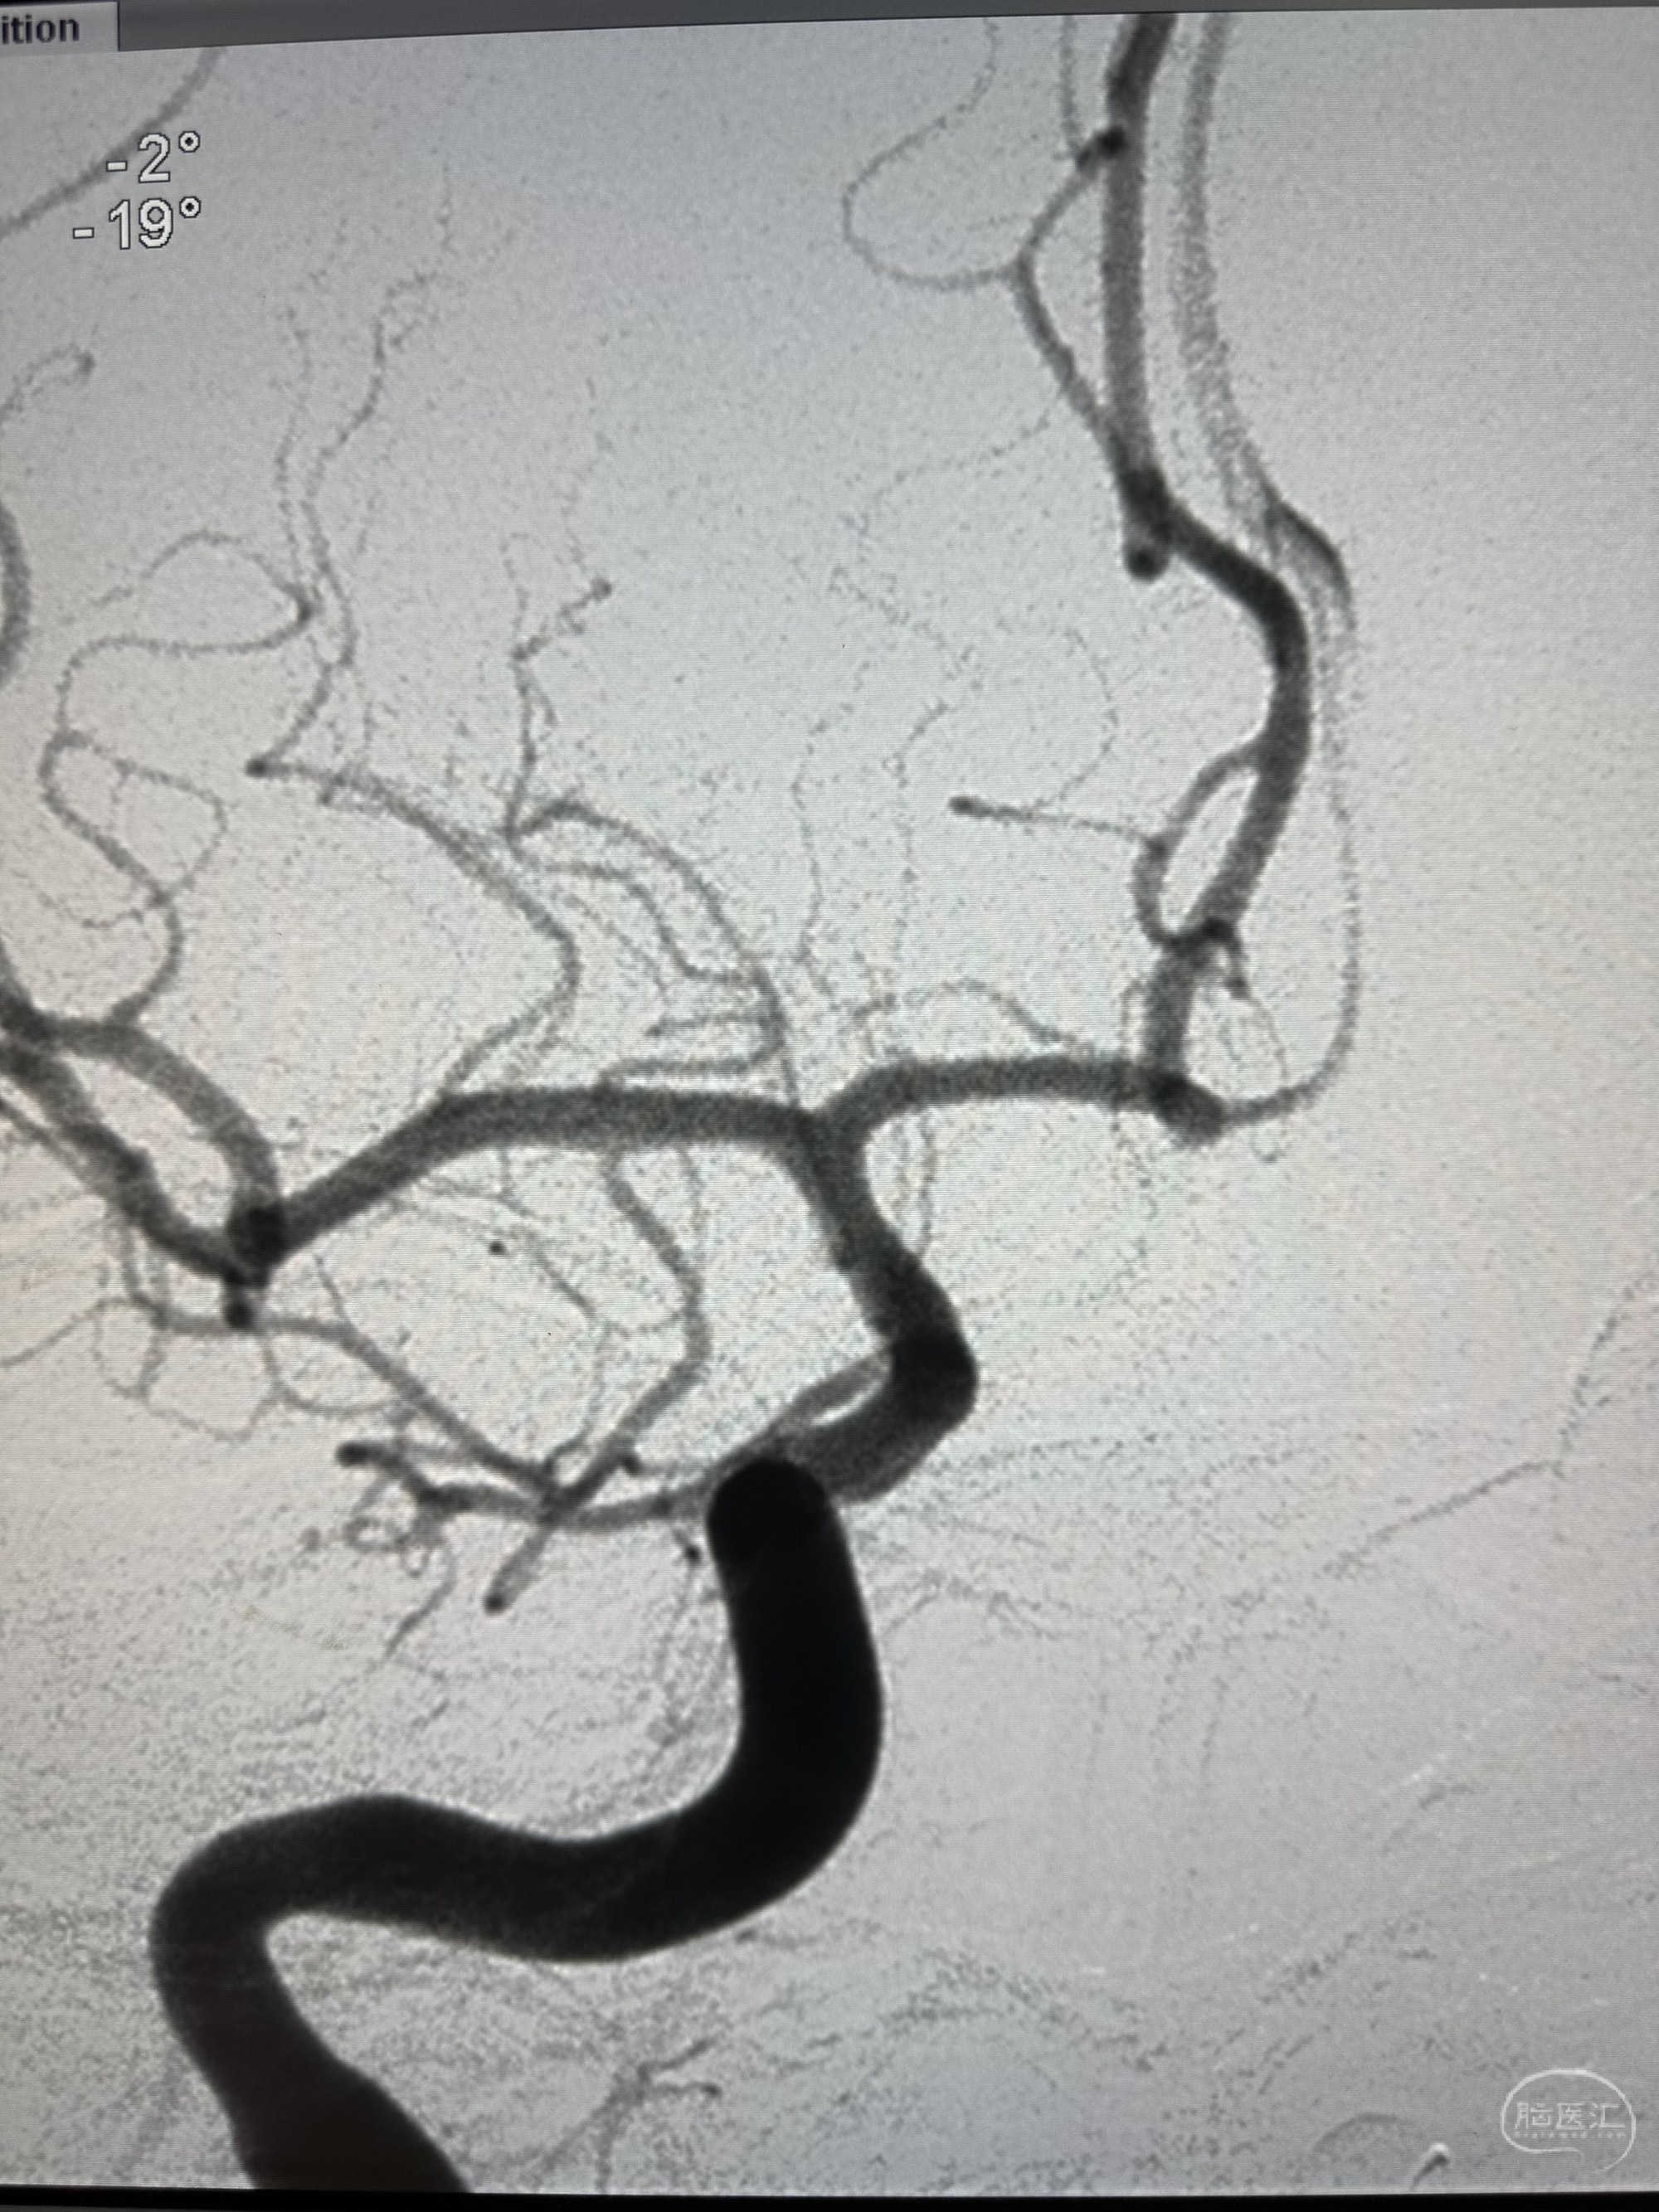

右侧颈内动脉造影感觉前交通有一个

侧位